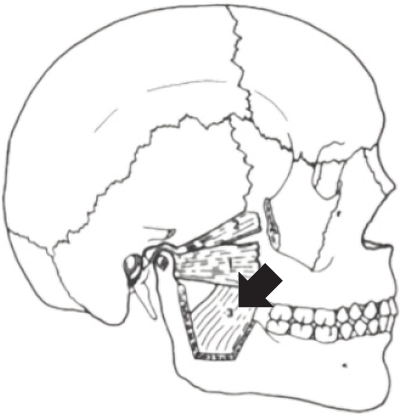

Sobre os músculos pertencentes ao grupo da mastigação, analise a imagem a seguir:

Disponível em: MADEIRA, MIGUEL CARLOS. Anatomia da face: Bases anatomofuncionais para a prática odontológica. 6ª ed.

O músculo indicado pela seta corresponde ao: